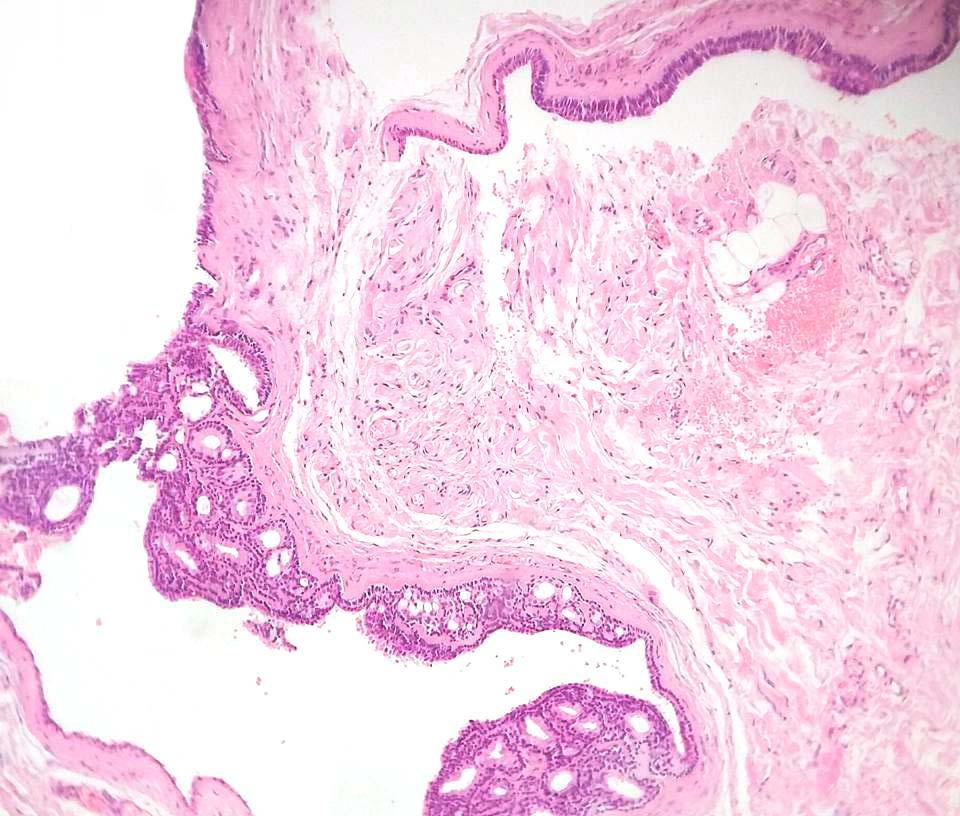

Histological features

•Pseudo-encapsulated unilocular or multilocular

•Outer myoepithelial cells & inner layer of columnar cells with eosinophilic cytoplasm showing decapitation secretion

•Adenomatous/papillary component (cystadenoma)